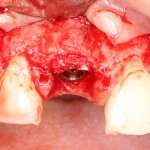

Устанавливается имплантат Astratech (Dentsply Implants):

Для аугментации также используем Bio-Oss Collagen 100 mg, нарезаем его по размеру с помощью скальпеля и позиционируем в лунках щечных корней:

На имплантат ставим формирователь, ушиваем лунку. Напомню, что любой биоматериал должен быть герметично запечатан в ране (фактор успеха III). В противном случае, от него больше вреда, чем пользы:

Совсем уж стягивать края раны не нужно (если бы мы использовали обычный Bio-Oss, то это было бы необходимо). Отличие Bio-Oss Collagen еще и в том, что он не размывается при кровотечении.